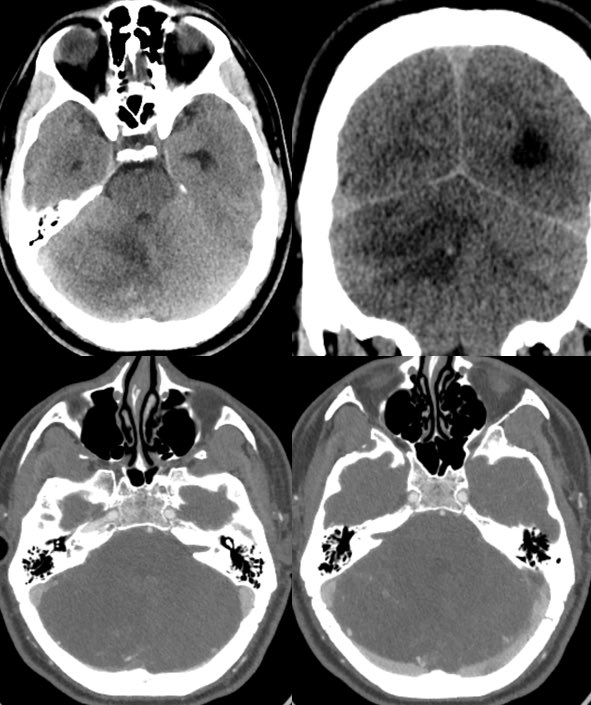

▶️Initial head CT demonstrates expansion and edema of the right cerebellar hemisphere. The overlying bones are unremarkable.

▶️CTA shows some peripheral increased vascularity but no thrombosis.